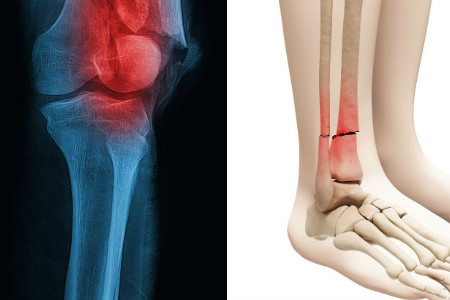

运动后骨头疼主要就是因为运动量多大导致的。每个人对于运动量的承受能力都是有限的,当身体承受不住的时候,就会导致一些症状的发生。运动过度会造成肌肉或骨膜的损伤,从而引起骨头的疼痛。严重的时候,甚至会导致骨骼变形引起骨折。因此,我们在平时运动的时候应该注意对运动量的控制,不要运动过度。

每一项运动都有其正确、标准的运动方法,我们需要学会这些正确的运动方法,这样才能达到运动的效果。如果运动的方法或姿势不正确,那就可能引起肌肉或骨头的疼痛。比如我们在跑步的时候,如果没有注意跑步的姿势、身体的发力部位等,那跑步过后就会出现身体疼痛。打篮球也一样,不正确的投篮姿势也会引起手腕骨骼疼痛。